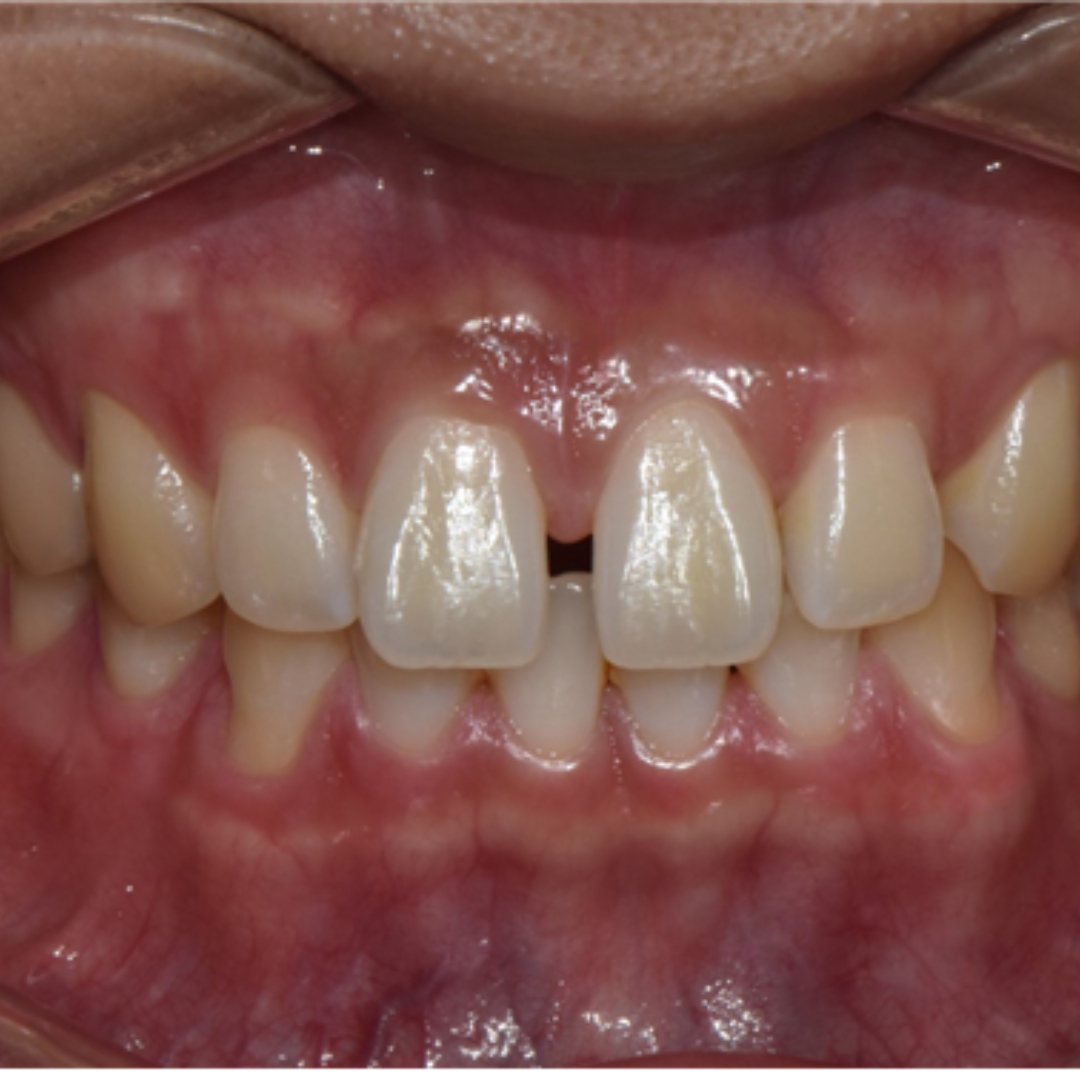

최근에는 티 나지 않는 교정을 원하시는 심미적인 이유 뿐만 아니라, 위생 관리, 음식물 섭취, 부상 방지 등 다양한 이유로 전통적인 부착식 교정장치 대신 투명 교정을 선택하시는 환자분들이 부쩍 많아지셨습니다. 투명 교정 치료는 결과는 동일하면서 사진 촬영, 운동, 여행 등 일상 생활에 제약이 크게 없다는 점이 큰 장점입니다. 다만, 증례에 따라 부착식 교정장치가 더 빠르고 효과적인 경우도 있어 교정 치료 전 전문의와의 상담을 통해 결정하는 것이 좋습니다. ^^ 총 32주 간의 교정 치료가 종료된 모습입니다. 기존에 가장 고민이셨던 공간 벌어짐, 정중선 불일치가 예쁘게 수정되었습니다. 2025.5.18.

치료 전, 후 미소가 눈에 띄게 개선되었습니다. 정면에서 두드러지게 보였던 정중 이개와 정중선 불일치가, 벌어진 공간이 폐쇄되고 가지런하게 배열되니 깔끔하고 정돈된 인상을 줍니다. 앞니의 벌어진 공간 폐쇄를 위해 라미네이트나 크라운 치료로 심미적이고 즉각적인 개선을 가져오는 경우도 있습니다. 하지만 위 환자분의 경우 다른 부정교합이 있기 때문에 교정 치료 없이 심미 보철을 진행했다면, 정중선 불일치가 잔존하거나, 앞니 크기가 비대칭적으로 마무리되었을 수 있습니다. 32주의 교정 치료로 자연스럽고 아름다운 미소를 회복하여 환자분도, 의료진도 만족한 결과를 얻어 성공적인 투명 교정 치료 증례로 소개드렸습니다. 세심한 진단과 맞춤형 치료계획으로 예쁜 미소를 찾아드립니다! 안전한 365서울앞선치과 교정 치료 많은 관심 부탁드립니다~!!

치료 전, 후 미소가 눈에 띄게 개선되었습니다. 정면에서 두드러지게 보였던 정중 이개와 정중선 불일치가, 벌어진 공간이 폐쇄되고 가지런하게 배열되니 깔끔하고 정돈된 인상을 줍니다. 앞니의 벌어진 공간 폐쇄를 위해 라미네이트나 크라운 치료로 심미적이고 즉각적인 개선을 가져오는 경우도 있습니다. 하지만 위 환자분의 경우 다른 부정교합이 있기 때문에 교정 치료 없이 심미 보철을 진행했다면, 정중선 불일치가 잔존하거나, 앞니 크기가 비대칭적으로 마무리되었을 수 있습니다. 32주의 교정 치료로 자연스럽고 아름다운 미소를 회복하여 환자분도, 의료진도 만족한 결과를 얻어 성공적인 투명 교정 치료 증례로 소개드렸습니다. 세심한 진단과 맞춤형 치료계획으로 예쁜 미소를 찾아드립니다! 안전한 365서울앞선치과 교정 치료 많은 관심 부탁드립니다~!! |